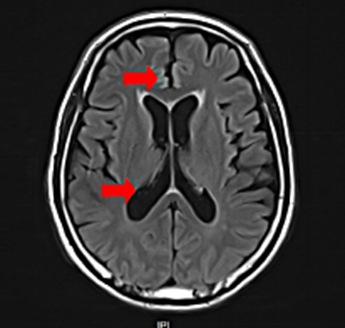

脑膜指的是颅骨与脑实质之间三层膜的结构,由外向内也就是从颅骨往里数分别是硬脑膜、蛛网膜、软脑膜,统称为脑膜,平时所说的脑膜转移指的是软脑膜转移,也就是软脑膜和蛛网膜下腔中间的脑脊液被肿瘤细胞侵入,随着脑脊液的循环播散造成整个神经系统的受累。

是肿瘤全中枢神经系统转移受累的特殊模式,是肿瘤致死性并发症,一旦发生脑膜转移,便意味着患者的疾病进程已经至晚期,病情进展迅速,预后差。临床表现有头痛、呕吐、后背痛、面神经麻痹、听力下降、声音嘶哑等,少数出现癫痫、行走不稳、精神障碍和记忆丧失,患者的生活质量受到极大影响,并且生存时间短。

脑膜转移的主要特点为肿瘤细胞侵入脑脊液中,并且随着脑脊液增殖散播,造成整个中枢神经系统的弥漫受累。由于血脑屏障的作用,全身系统给药时,药物难以进入脑脊液。脑脊液药物浓度无法有效控制其中的肿瘤细胞,因此,将抗肿瘤化疗药物直接注入脑脊液中(鞘内化疗)是该病主要治疗方式。